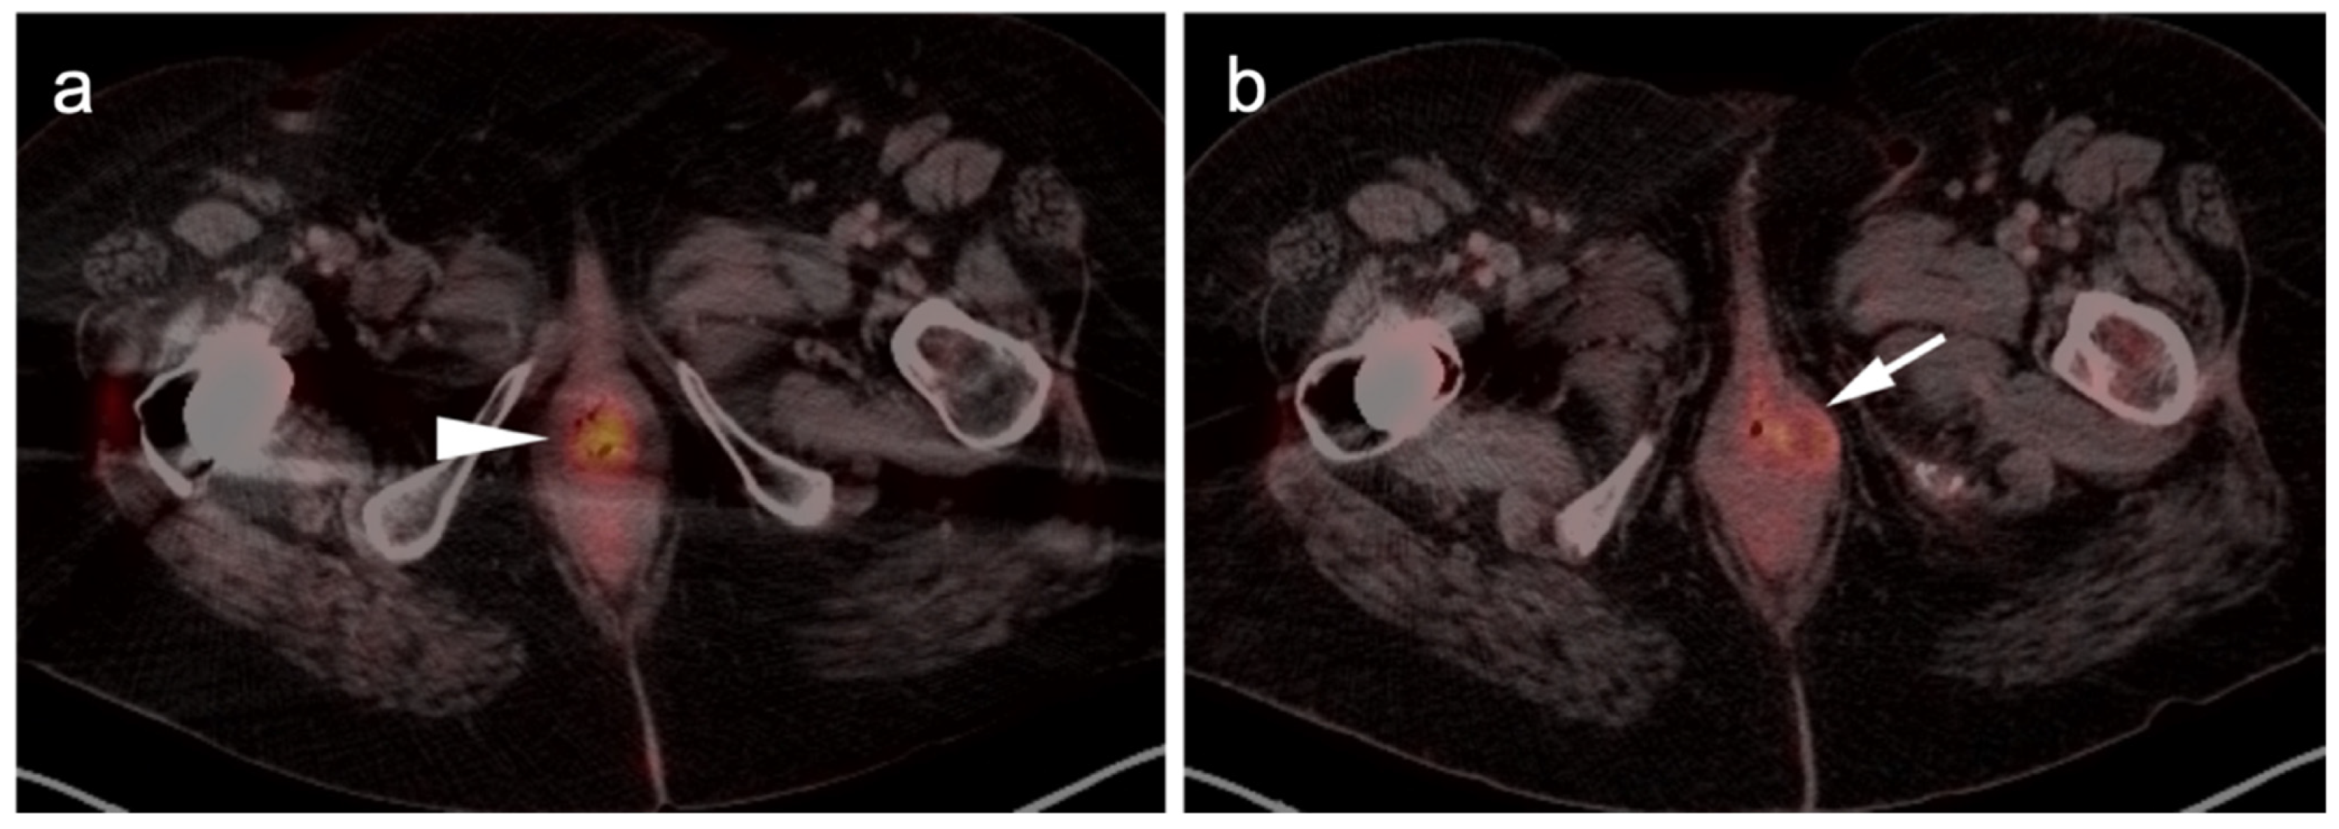

2.3.3. Mucosal Melanoma